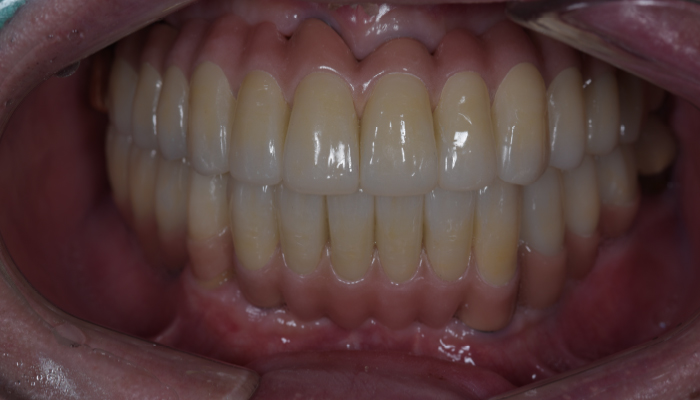

틀니 임플란트 전후 사례

• 식립 전

식립 후